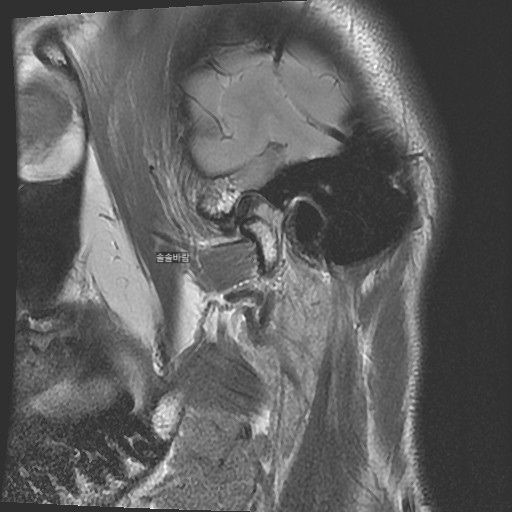

구강내과 턱 MRI 어느 사진이 우측? 좌측?인지 어떻게 보나요? 디스크 두꺼워짐 심한가요?ㅜ

구강내과 턱 MRI 사진 보는데 귀 위치가 다 똑같아서요

어느 사진이 우측? 좌측?인지 어떻게 보나요?

그리고 사진 상 디스크 두꺼워짐 심한가요?ㅜ

현재 사진만으로는 정확히 왼쪽이나 오른쪽이다 라고 할 수 없습니다. 이는 데이터 상의 reference가 필요하며 보통은 해당 부위가 질문자님 기준으로 좌측일 가능성이 가장 크나 이는 좌우 반전을 할 수 있기 때문에 무조건 좌측이라고 할 수 없습니다. 현재 개구시와 폐구시에 보았을 때 condyle (아래턱 부위의 일부)가 disc를 넘어가지 못하고 있으며 이러한 경우 개구제한이 있거나 넘어가더라도 소리가 나면서 넘어갈 수 있습니다. 일부 염증도 보이고 있으므로 내과적인 치료를 하셔야 할 것으로 보입니다.